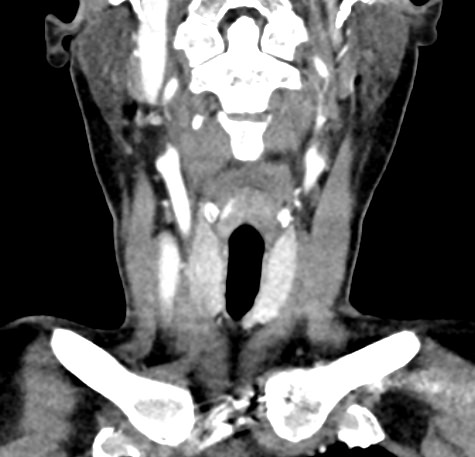

КТ щитовидной железы часто используется в диагностике доброкачественных и злокачественных опухолей железы, оценки распространенности процесса, поэтому для улучшения визуализации патологических очагов дополнительно применяется внутривенное болюсное контрастирование. Методика контрастирования позволяет увидеть на снимке опухоли минимальных размеров за счет того, что контраст избирательно накапливается в измененных тканях и обеспечивает яркое изображение патологического очага на фоне здоровых окружающих тканей.  Контрастирование дает возможность определить врачу границы опухоли, ее размеры, степень васкуляризации, точное расположение, особенно это важно при нетипичной (загрудинной) локализации органа.

В наших центрах обследование щитовидной железы выполняется на современных мультиспиральных томографах TOSHIBA AQUILION, оснащенных увеличенным количеством сверхчувствительных детекторов, позволяющих производить множество срезов с минимальной толщиной от 0,5 мм. Инновационные возможности аппаратов обеспечивают получение множества послойных снимков высокого качества и построение на их основе трехмерной модели органа. Кроме того, аппаратура позволяет за счет сокращения времени сканирования минимизировать лучевую нагрузку на пациента.

Мультиспиральная компьютерная томография позволяет точно определить размеры и расположение щитовидной железы, выявить опухолевые образования, оценить их структуру, степень кровоснабжения, взаимодействие с окружающими тканями.